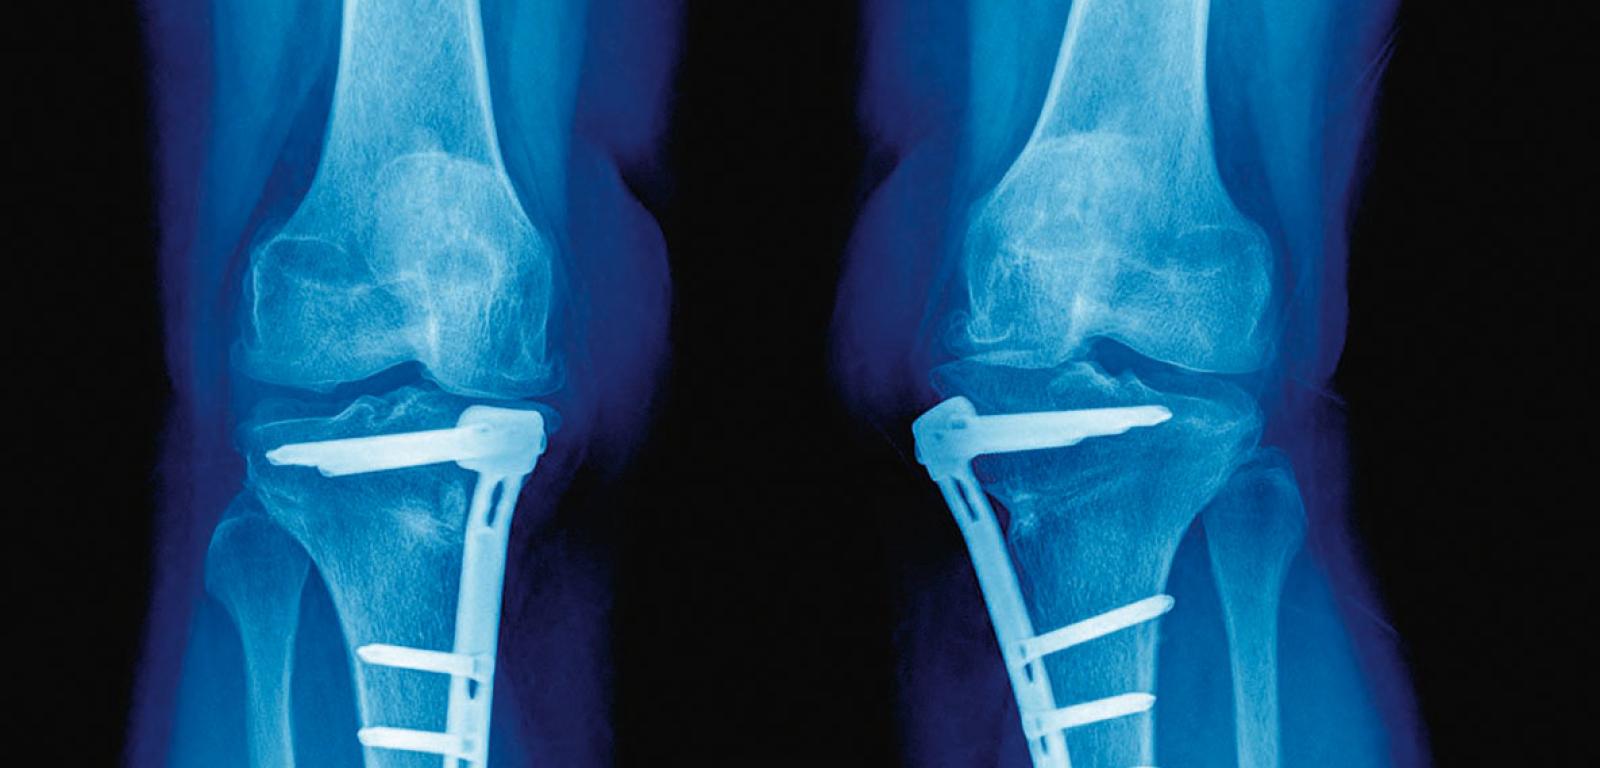

Ceramiczny implant 3D do leczenia złamań

Jeśli dojdzie do złamania prostego kości, wystarczy odpowiednio ją zestawić, całość zagipsować i poczekać, aż natura sama się z tym upora. Często jednak mamy do czynienia ze złamaniami skomplikowanymi, wieloodłamowymi. W tych przypadkach interwencja ortopedyczna jest znacznie bardziej złożona. Niezbędne staje się wykonanie wielu operacji (stosuje się np. specjalne metalowe śruby czy płytki), a ich efekt bywa niezadowalający.

Naukowcy z University of Sydney w Australii postanowili podejść do tego problemu w zupełnie nowy sposób. Od jakiegoś czasu próbują leczyć złamania specjalnymi implantami – ceramicznymi rusztowaniami, które wykonuje się metodą druku 3D z biokompatybilnych minerałów (m.in. hardystonit i gahnit). Pierwsze eksperymenty przeprowadzono na kościach ramiennych u królików. Ponieważ wyniki okazały się bardzo obiecujące, w kolejnych doświadczeniach badano złamania kości długich u owiec. Okazało się, że po wprowadzeniu implantów do kości zwierzęta mogły od razu chodzić (kończyny stabilizowano opatrunkiem gipsowym), a po roku 88% owiec całkowicie wyzdrowiało. Co więcej, w miarę narastania nowej tkanki kostnej materiał ceramiczny ulegał powolnemu rozpuszczaniu, a więc nie trzeba było na koniec usuwać implantów.